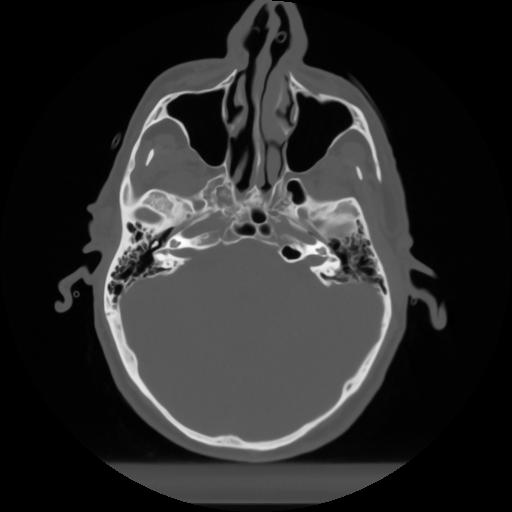

10 P.BLANDAS,,Axial,2.0,P.BLANDAS,,